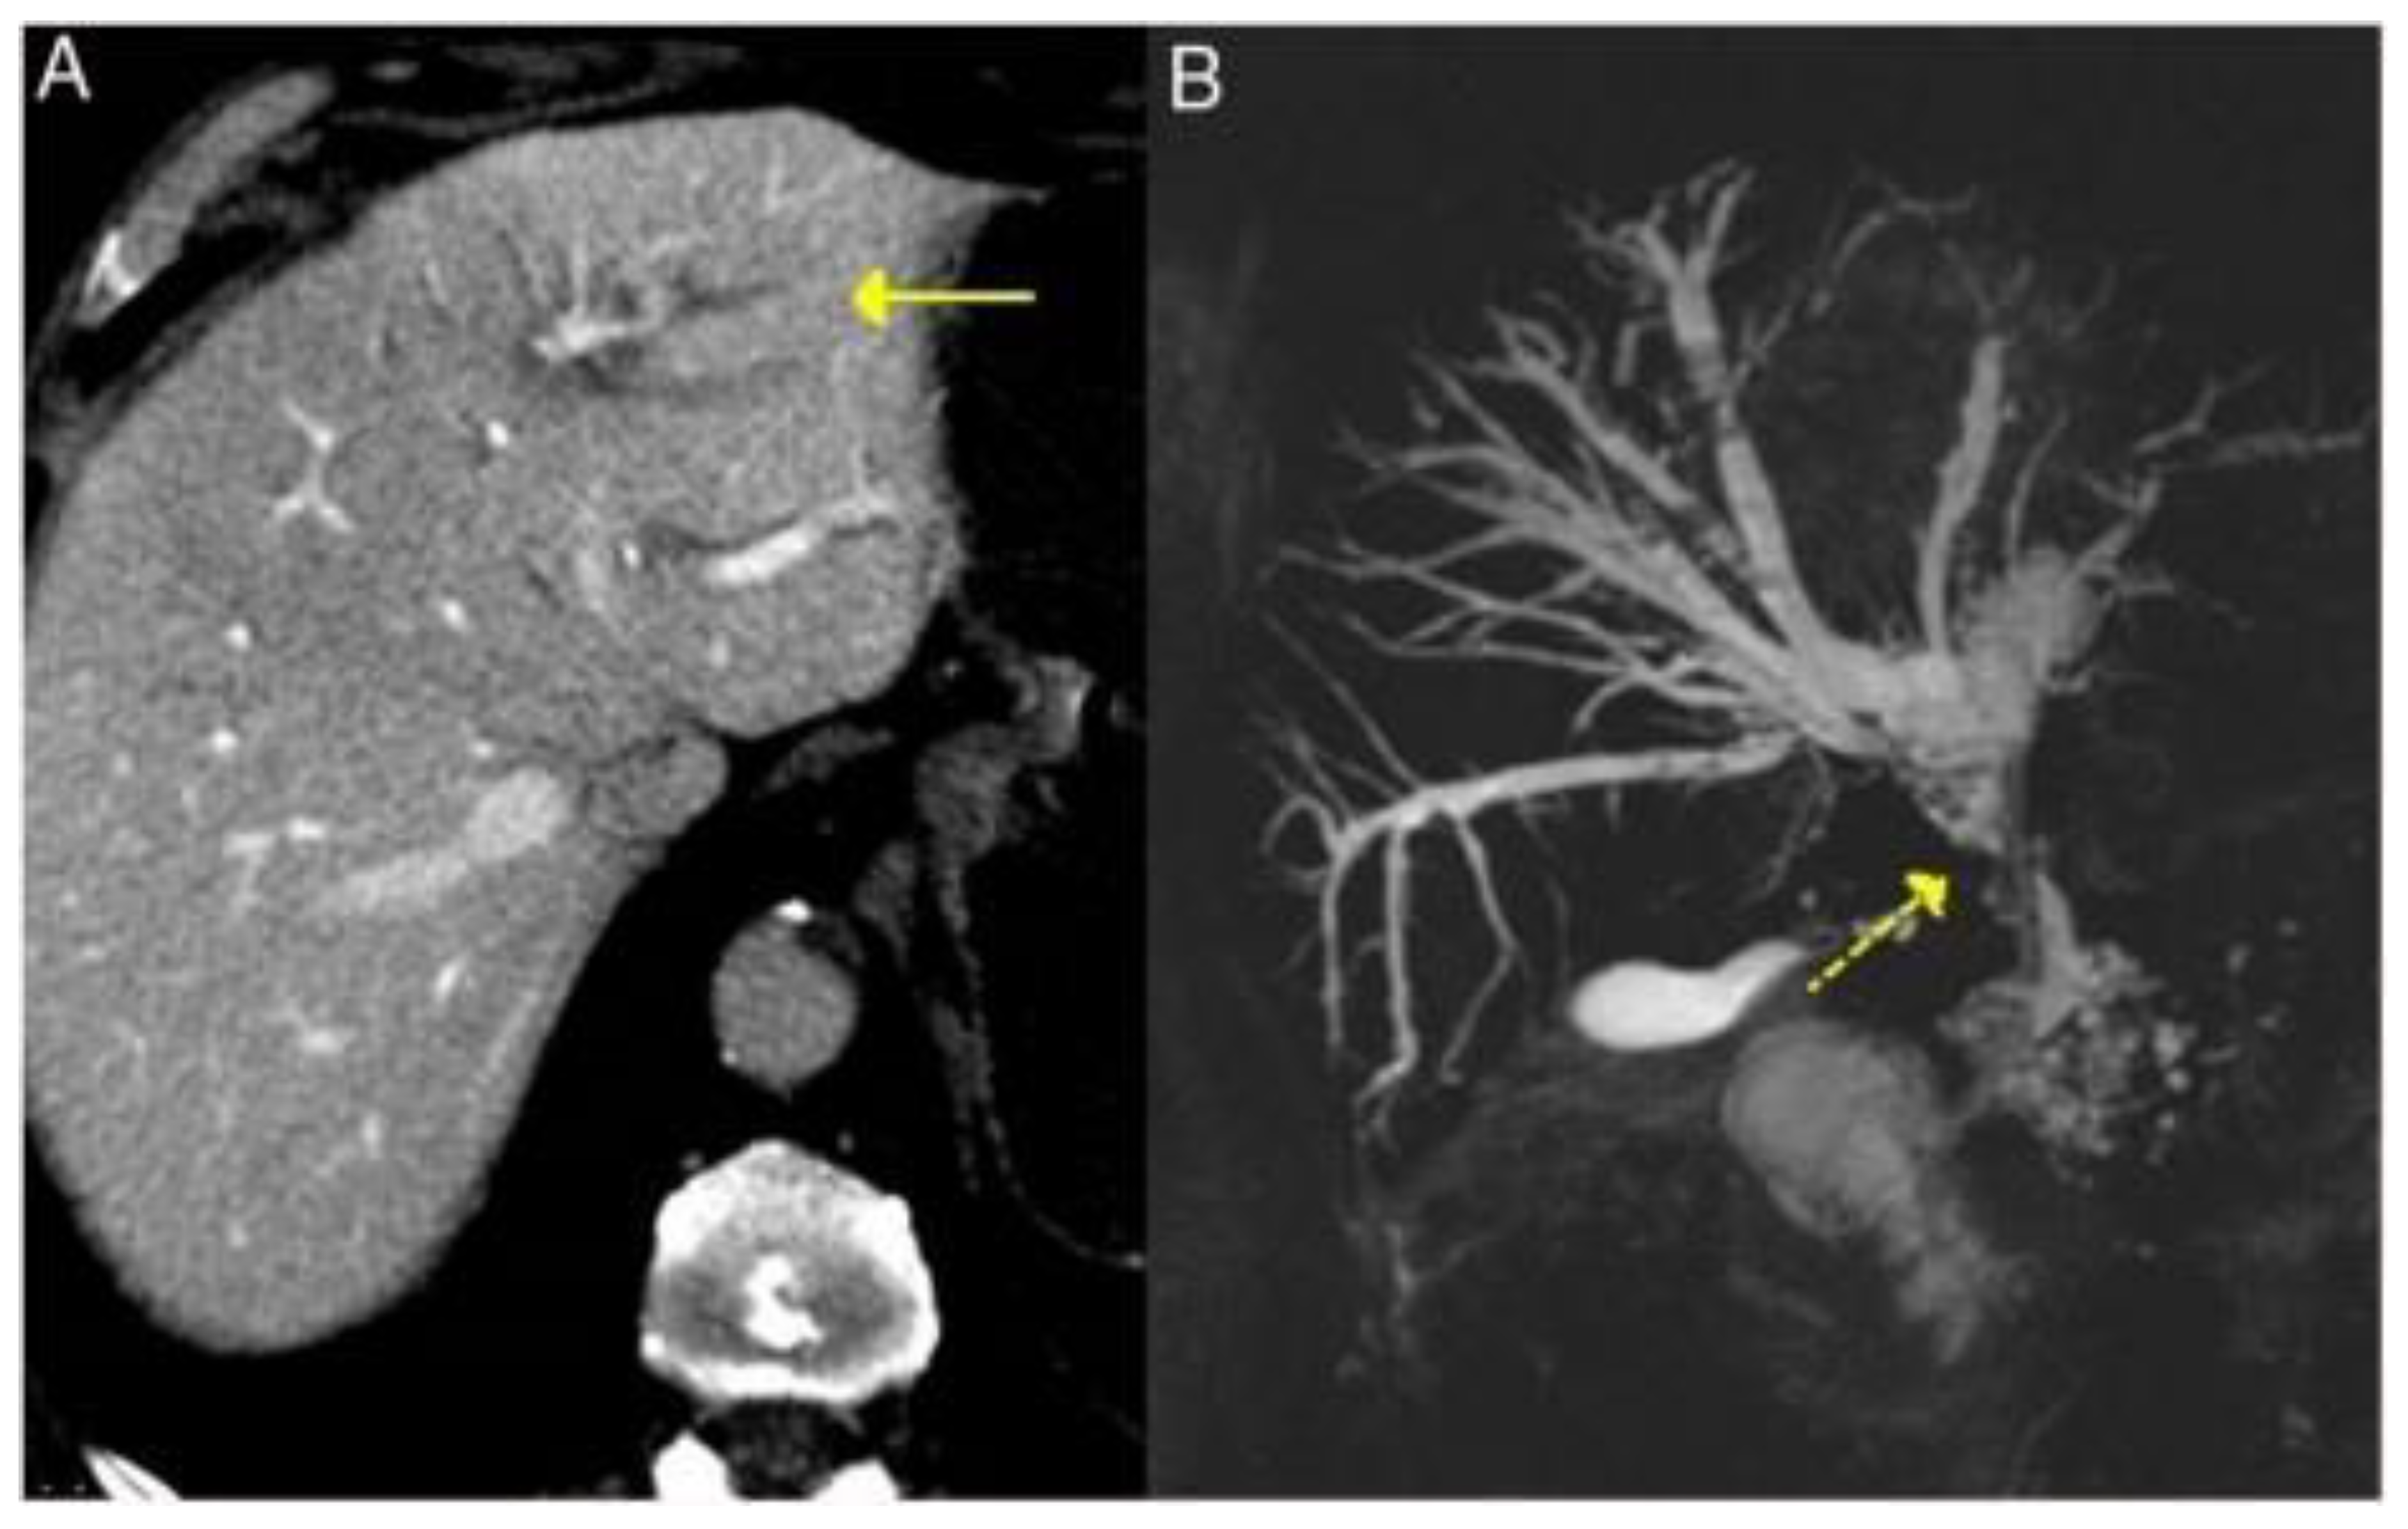

3.2.4. Liver and Bile Ducts

3.3.4. Liver and Bile Ducts